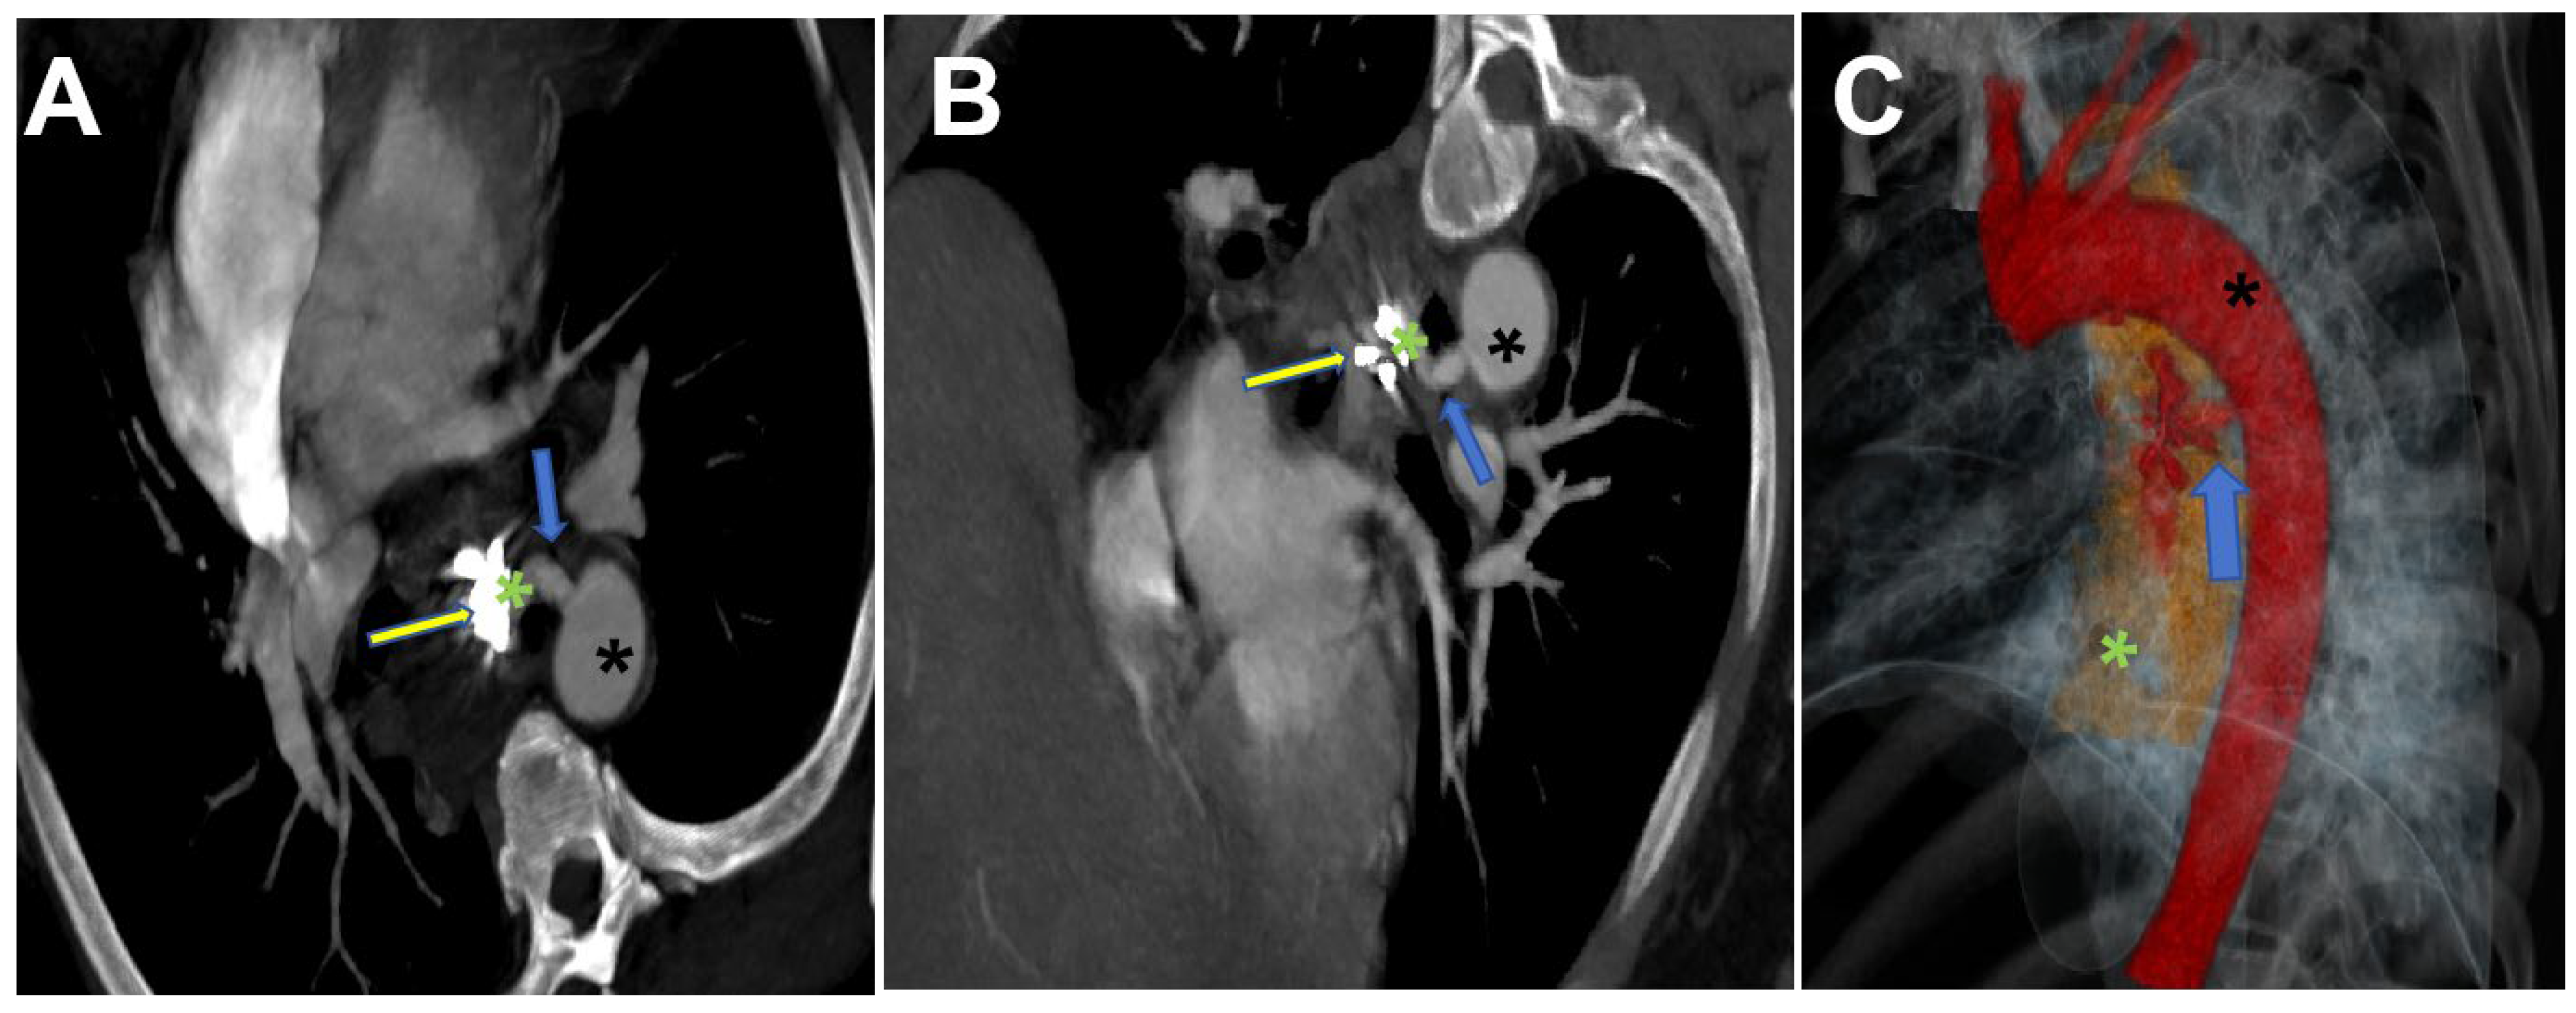

2. Case Report